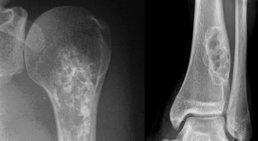

Knochen- und Weichteiltumore

Knochen- und Weichteiltumore sind selten und können in gut- und bösartige Gewächse unterteilt werden. Eine frühzeitige, korrekte Diagnostik und Therapieplanung sind entscheidend für den Behandlungserfolg. Daher sollte bei Vorliegen eines Tumors des Bewegungsapparates ein Fac...